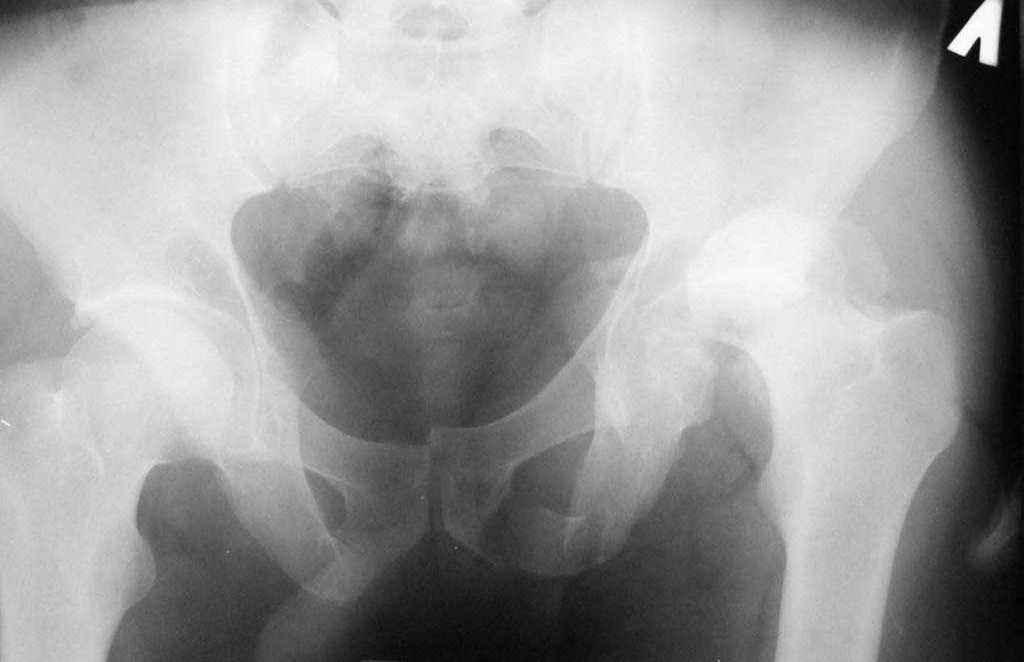

[Ortho] перелом вертлужной впадины

Досылаю рентгенограмму